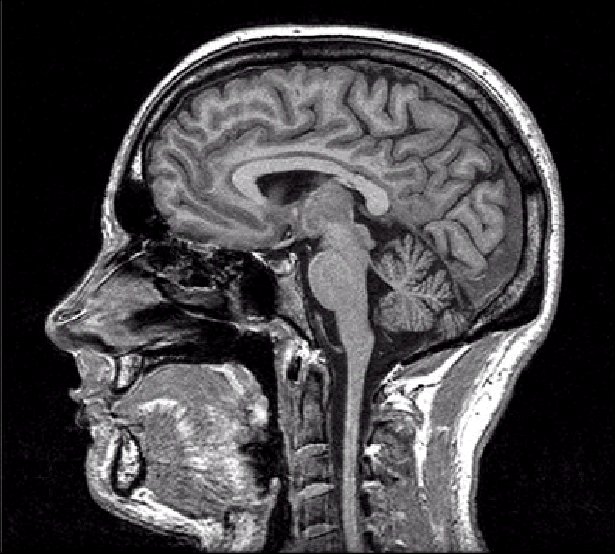

[في اليمين دماغ شخص طبيعي، في اليسار دماغ الرجل]

اظهر الفحص شيئا استثنائيا: كانت جمجمته مليئة بالسائل النخاعي إلى حد كبير ولم يتبقى الا طبقة رقيقة فقط من نسيج الدماغ. تعرف هذه الحالة باسم الاستسقاء الدماغي او hydrocephalus

لكن مدى حالته غير مسبوق،كان فاقد لـ 90% من كتلة دماغه، بمعنى انه يعيش بـ 10% دماغ